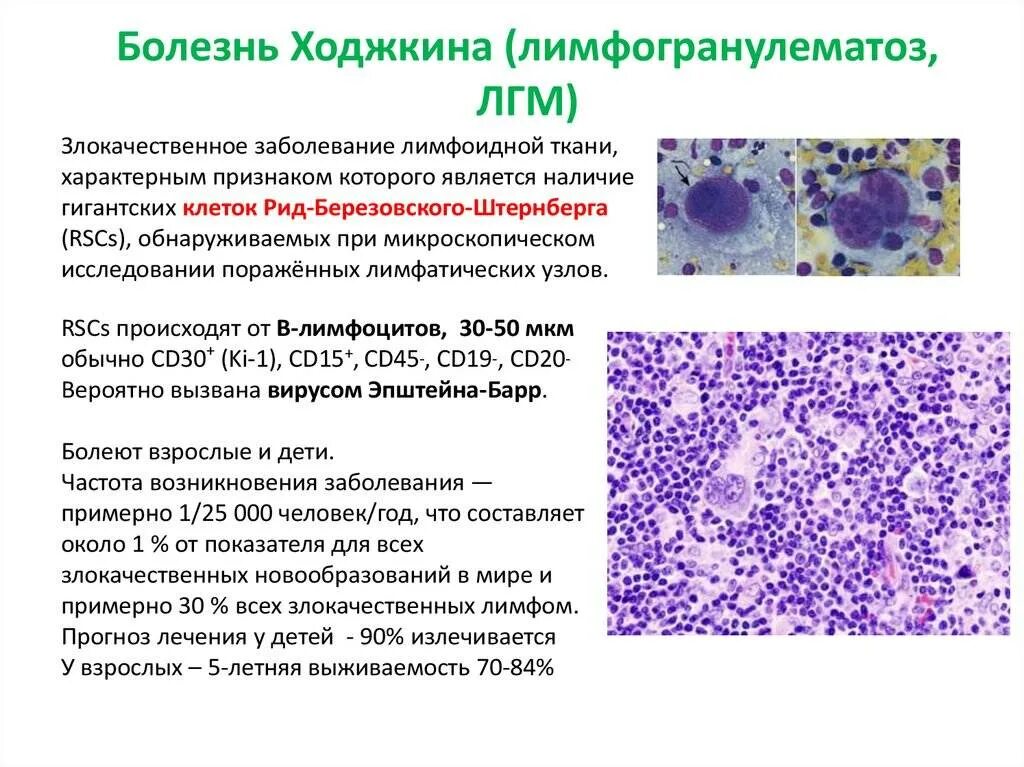

Злокачественная опухоль. Злокачественные новообразования. Опухолевые заболевания мозга. Лимома Беркита Тип злокачесивенных клеток. Клетки Березовского-Штернберга морфология. Ходжкинская лимфома морфология. Цитологическая картина лимфомы Ходжкина.

Лимома Беркита Тип злокачесивенных клеток. Клетки Березовского-Штернберга морфология. Ходжкинская лимфома морфология. Цитологическая картина лимфомы Ходжкина. Кт при опухоли надпочечников. Кортикостерома надпочечника кт. МСКТ объемное образование надпочечника. Кт мрт аденома надпочечника.